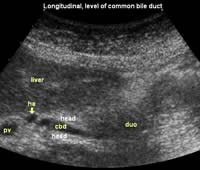

Longitudinal planes from right to left:

![]() Image21 |